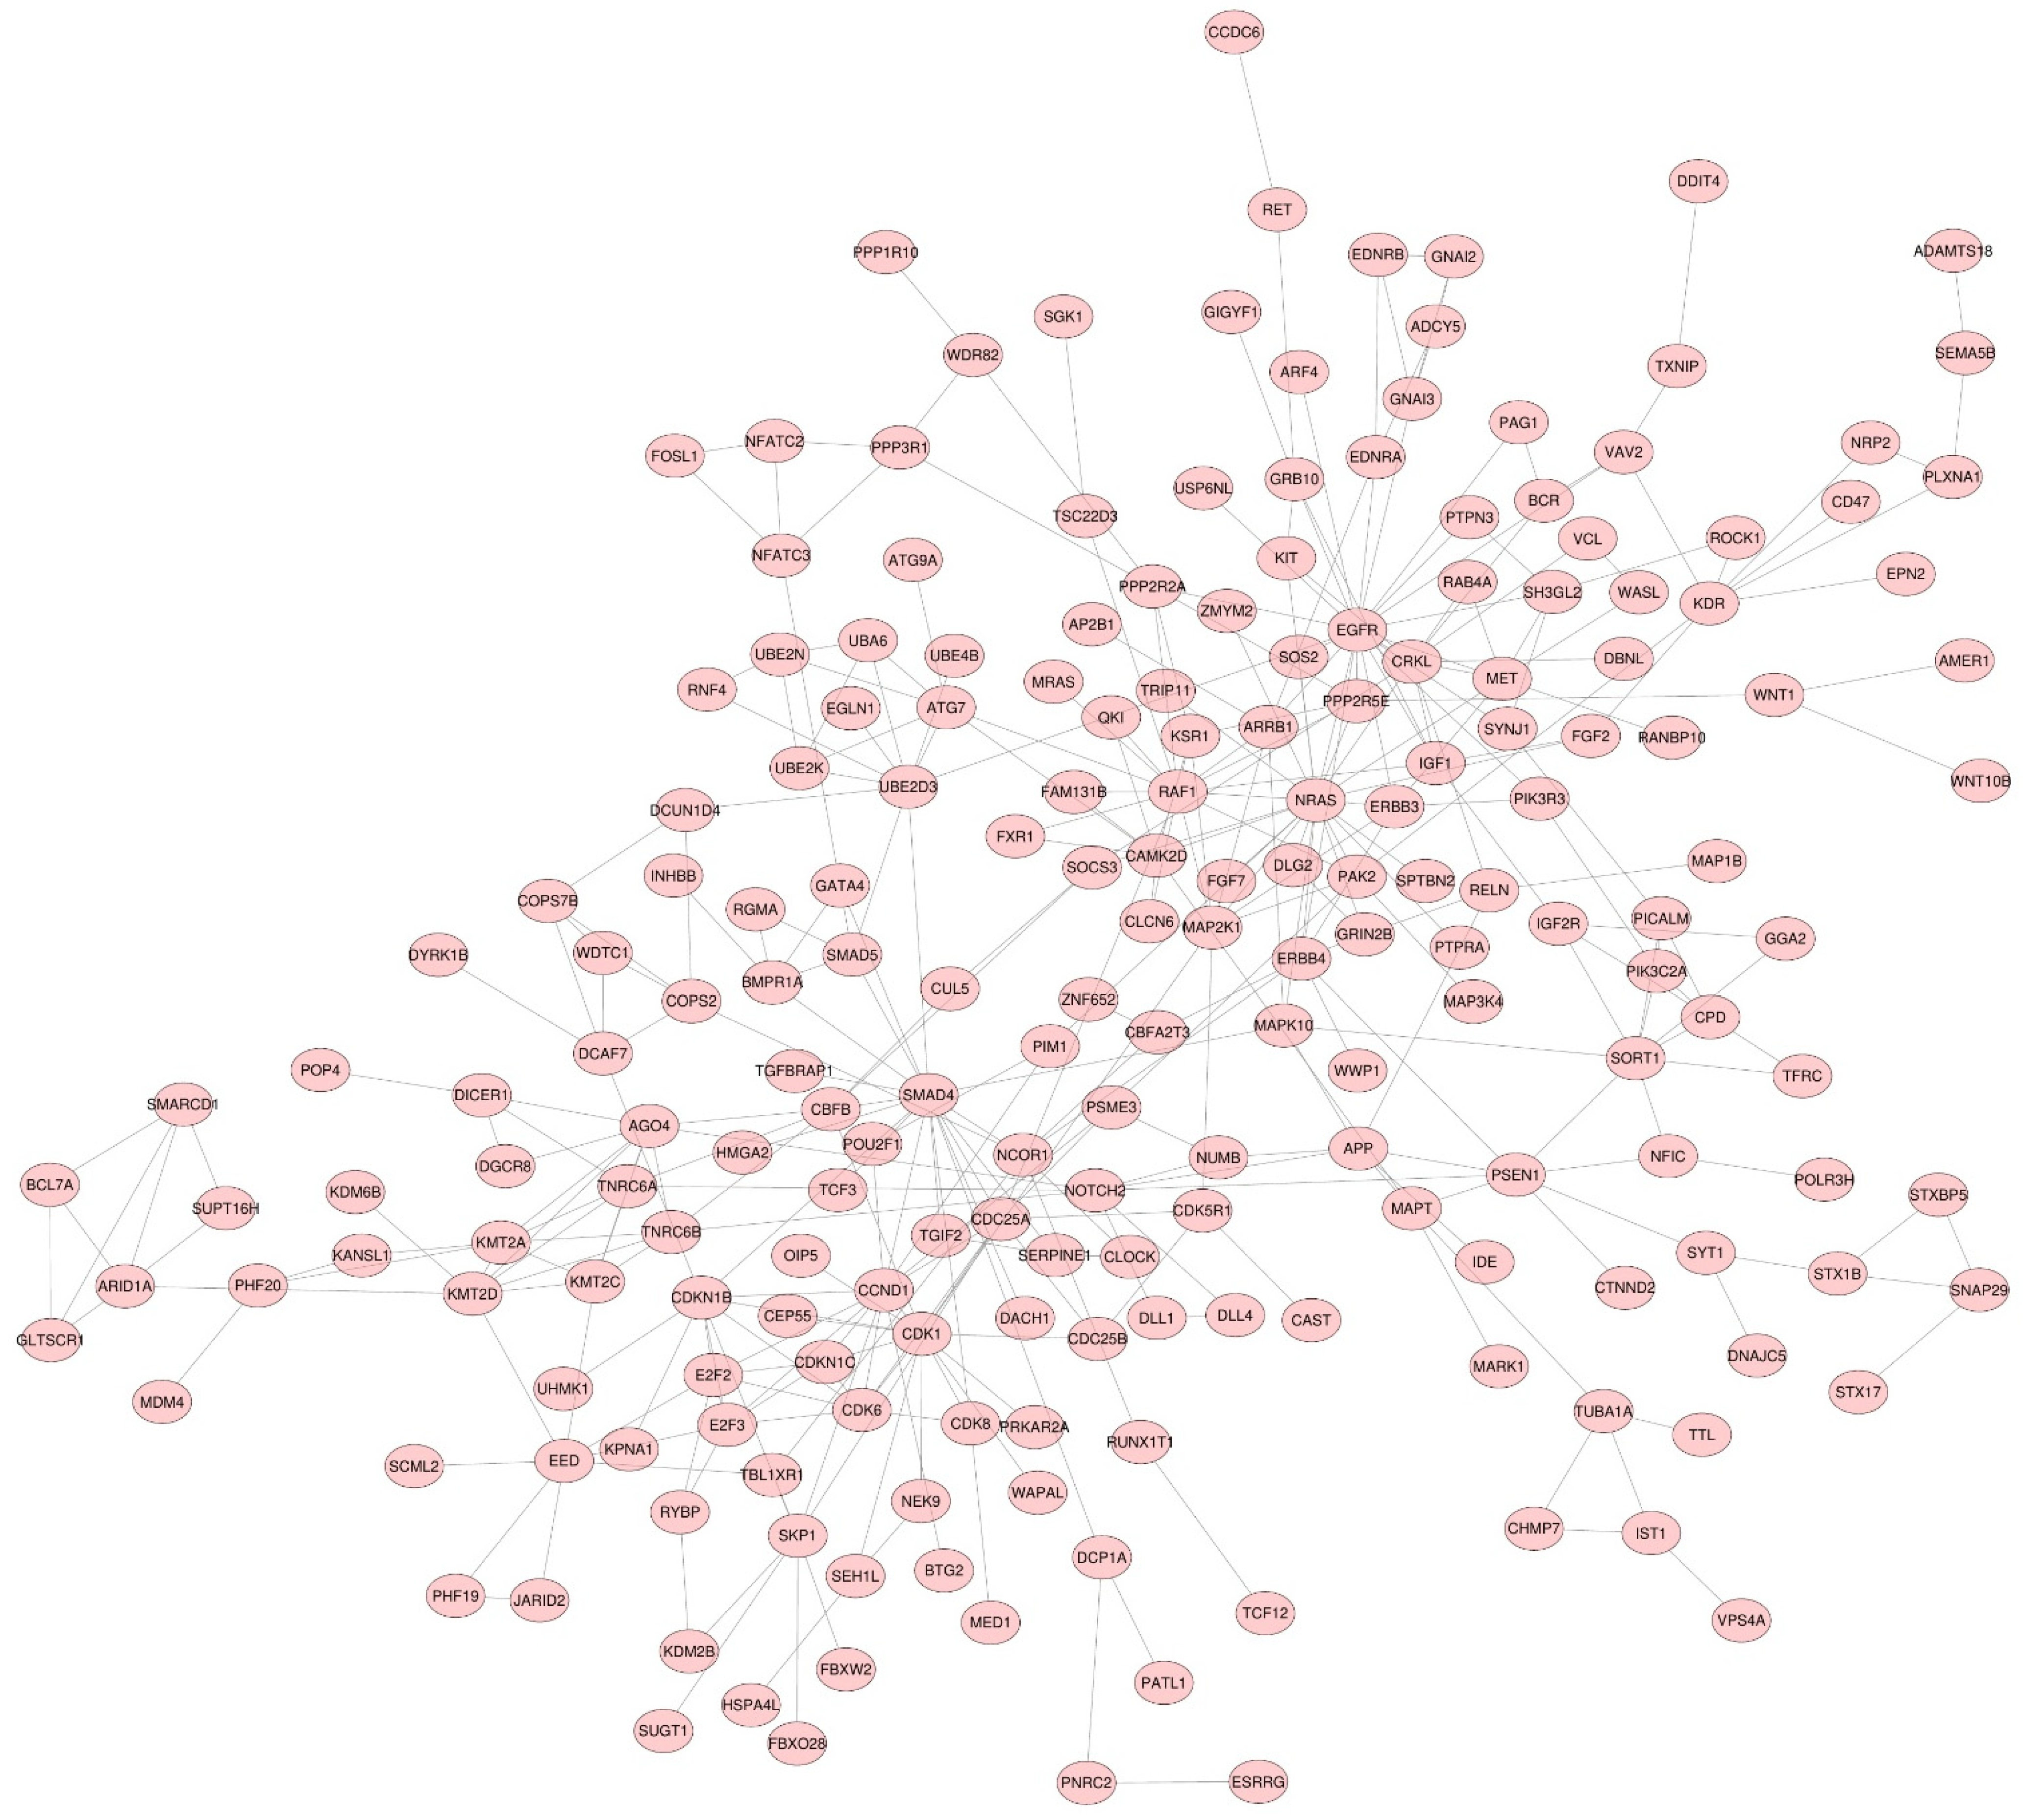

3.2. miRNA Target Genes

3.3. Functional Enrichment Analysis